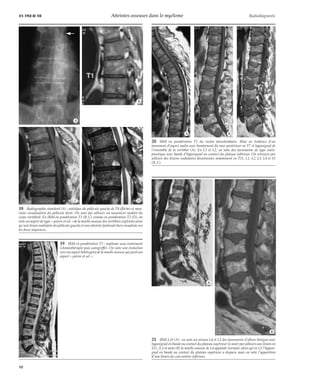

Résultats [6, 17, 18, 20, 23, 24, 30]

La sémiologie IRM des lésions du myélome comporte plusieurs

aspects, certains d’entre eux étant tout à fait non spécifiques,

d’autres pouvant être retrouvés dans d’autres pathologies

hématologiques comme les leucémies ou les lymphomes.

On distingue les lésions focales et les envahissements diffus.

– Les lésions focales : il s’agit d’images en hyposignal T1,

hypersignal T2 et se rehaussant après injection. Elles sont arrondies,

de taille et nombre variables. Elles peuvent être nodulaires et ne pas

entraîner de déformation des contours vertébraux (fig 13) ; à

l’inverse il peut s’agir de masse soufflante volumineuse (fig 14).

– Les envahissements diffus : ils sont de deux types :

– on peut observer un hyposignal diffus homogène en

pondération T1 (fig 15) (on retient comme hyposignal de la moelle

osseuse un signal inférieur à celui des disques intervertébraux).

En pondération T2 et après injection, le signal se rehausse

généralement. Cet aspect intéresse la totalité des vertèbres

explorées ;